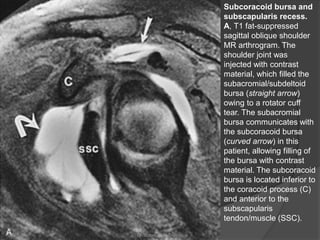

Alterações Diversas das

Cápsulas, Bolsas e Tendões

 Bursite Subcoracóide:

 Estrutura anatômica normal, localizada anteriormente

ao músculo subescapular e seu tendão,

 Comunica-se com o recesso glenoumeral ou com o

recesso subescapular da articulação do ombro →

derrame articular → bursite?

 Em 20% dos pacientes, ela se comunica com a bolsa

subacromial / subdeltóide.

 RM:

○ É identificada apenas se inflamada e preenchida com

líquido ou sinovite.

○ Localizada inferiormente ao processo coracóide e

anteriormente ao músculo subescapular, mais bem

visto em imagens sagitais oblíquas.

Subcoracoid bursa and

subscapularis recess.

A, T1 fat-suppressed

sagittal oblique shoulder

MR arthrogram. The

shoulder joint was

injected with contrast

material, which filled the

subacromial/subdeltoid

bursa (straight arrow)

owing to a rotator cuff

tear. The subacromial

bursa communicates with

the subcoracoid bursa

(curved arrow) in this

patient, allowing filling of

the bursa with contrast

material. The subcoracoid

bursa is located inferior to

the coracoid process (C)

and anterior to the

subscapularis

tendon/muscle (SSC).